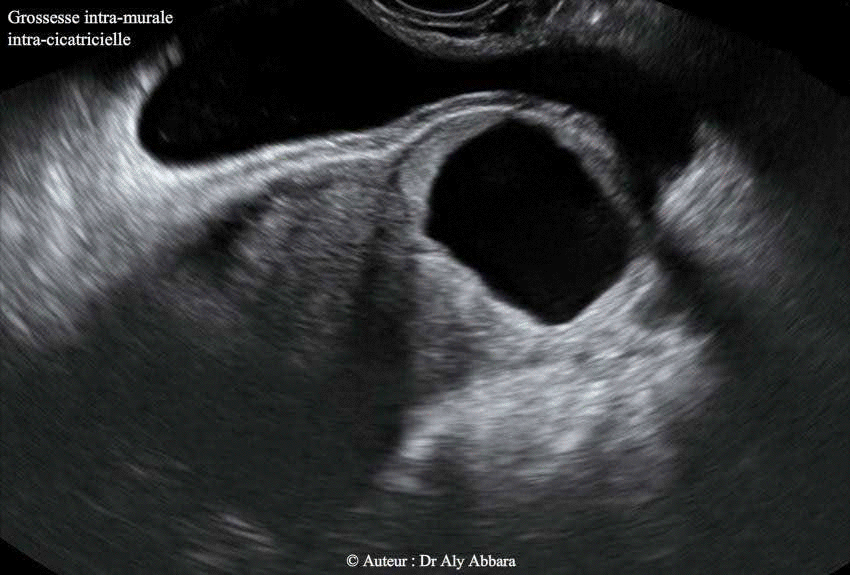

Grossesse ectopique intramurale sur utérus cicatriciel

• Images échographiques par voie endovaginale montrant un sac gestationnel d'une grossesse débutante et partiellement intramurale, implantée dans le site de la cicatrice de l'hystérotomie segmentaire transversale d'une ancienne césarienne.

Le 04.10.2012 (5+2 SA) -J0- : la patiente consulte aux urgences pour légère douleur pelvienne sans métrorragie ; l'examen clinico-échographique permet de mettre en évidence le diagnostic d'une grossesse débutante implantée dans le site de l’ancienne cicatrice de l’hystérotomie segmentaire transversale de l'ancienne césarienne ; il s'agissait d'un sac gestationnel de (20 x 12 8,5 mm) de diamètre, contenant une vésicule vitelline sans image embryonnaire.